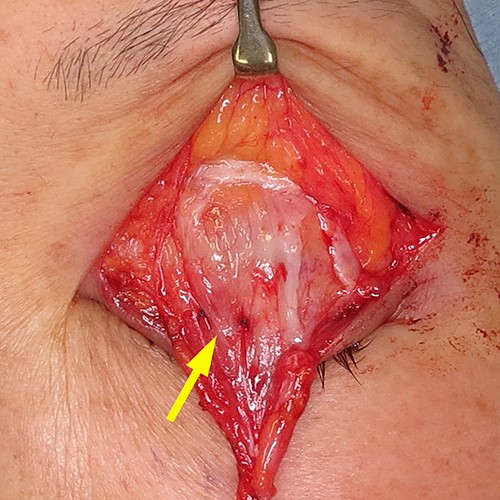

The operation involved LPS advancement with excision of redundant eyelid skin under local anesthesia. First, skin and orbicularis oculi were excised, and the orbital septum was incised horizontally to open the LPS aponeurosis behind the preaponeurotic fat pad. Next, the aponeurosis was slightly pulled out and secured to the tarsus with two stiches of 6/0 polypropylene (Fig. 3).

Surgical technique. The aponeurosis was slightly pulled out and secured to the tarsus with two stiches of 6/0 polypropylene (yellow arrow).